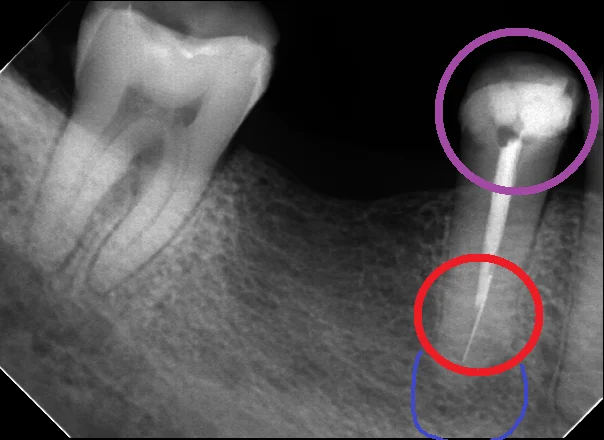

例えば、この方・・・

もうほとんど歯が残っていない状況にも関わらず、無理やりレジンで治療をされています。

(紫の丸の部分)

当然強度が足らないわけですから、複数箇所に亀裂が入っており、至る所が虫歯になってしまっています。

通常はここまでの状況になる前に痛みが出るのですが・・・

この方は神経の治療をされており、既に神経が無い状態になってしまっています。

そのため、防御反応である痛みが生じなかったわけですね。

ちなみに、この神経の治療も、根の先の方に器具が折れて入り込んでしまっています。(赤い丸の部分)

神経の治療の際に使う細い針金のような器具(ファイルやリーマー)があります。

これらは細い金属を使用しているため、何回も使うと金属疲労を起こし、このように折れてしまう事があります。

これ自体はただの偶発症の1つですし、正直そこまで珍しいわけでもありません。

私も年に数回は根の中に器具が折れてしまうという事はあります。

ただ、私の場合は折れたものはほとんどは自分で除去可能なのでそんなに問題にはなりません。

そして、器具が折れていても、根の先に膿などが溜まっていなければ特に問題は無いのですが・・・

今回のケースでは根の先にそこそこなサイズの膿が溜まっている様子(青い丸の部分)

このファイルなどは通常滅菌されたものを使用しているため、折れたところでこれが原因で感染を起こすことはありません。

ただし、今回のように神経の治療後に不適切な材料で治療されてしまった場合は、根の中に虫歯が入り込むことで再感染を起こします。

そしてその後ファイルがあると綺麗に出来ないところにまで感染が起こってしまうと、除去しないことには綺麗に治せないという事もあります。